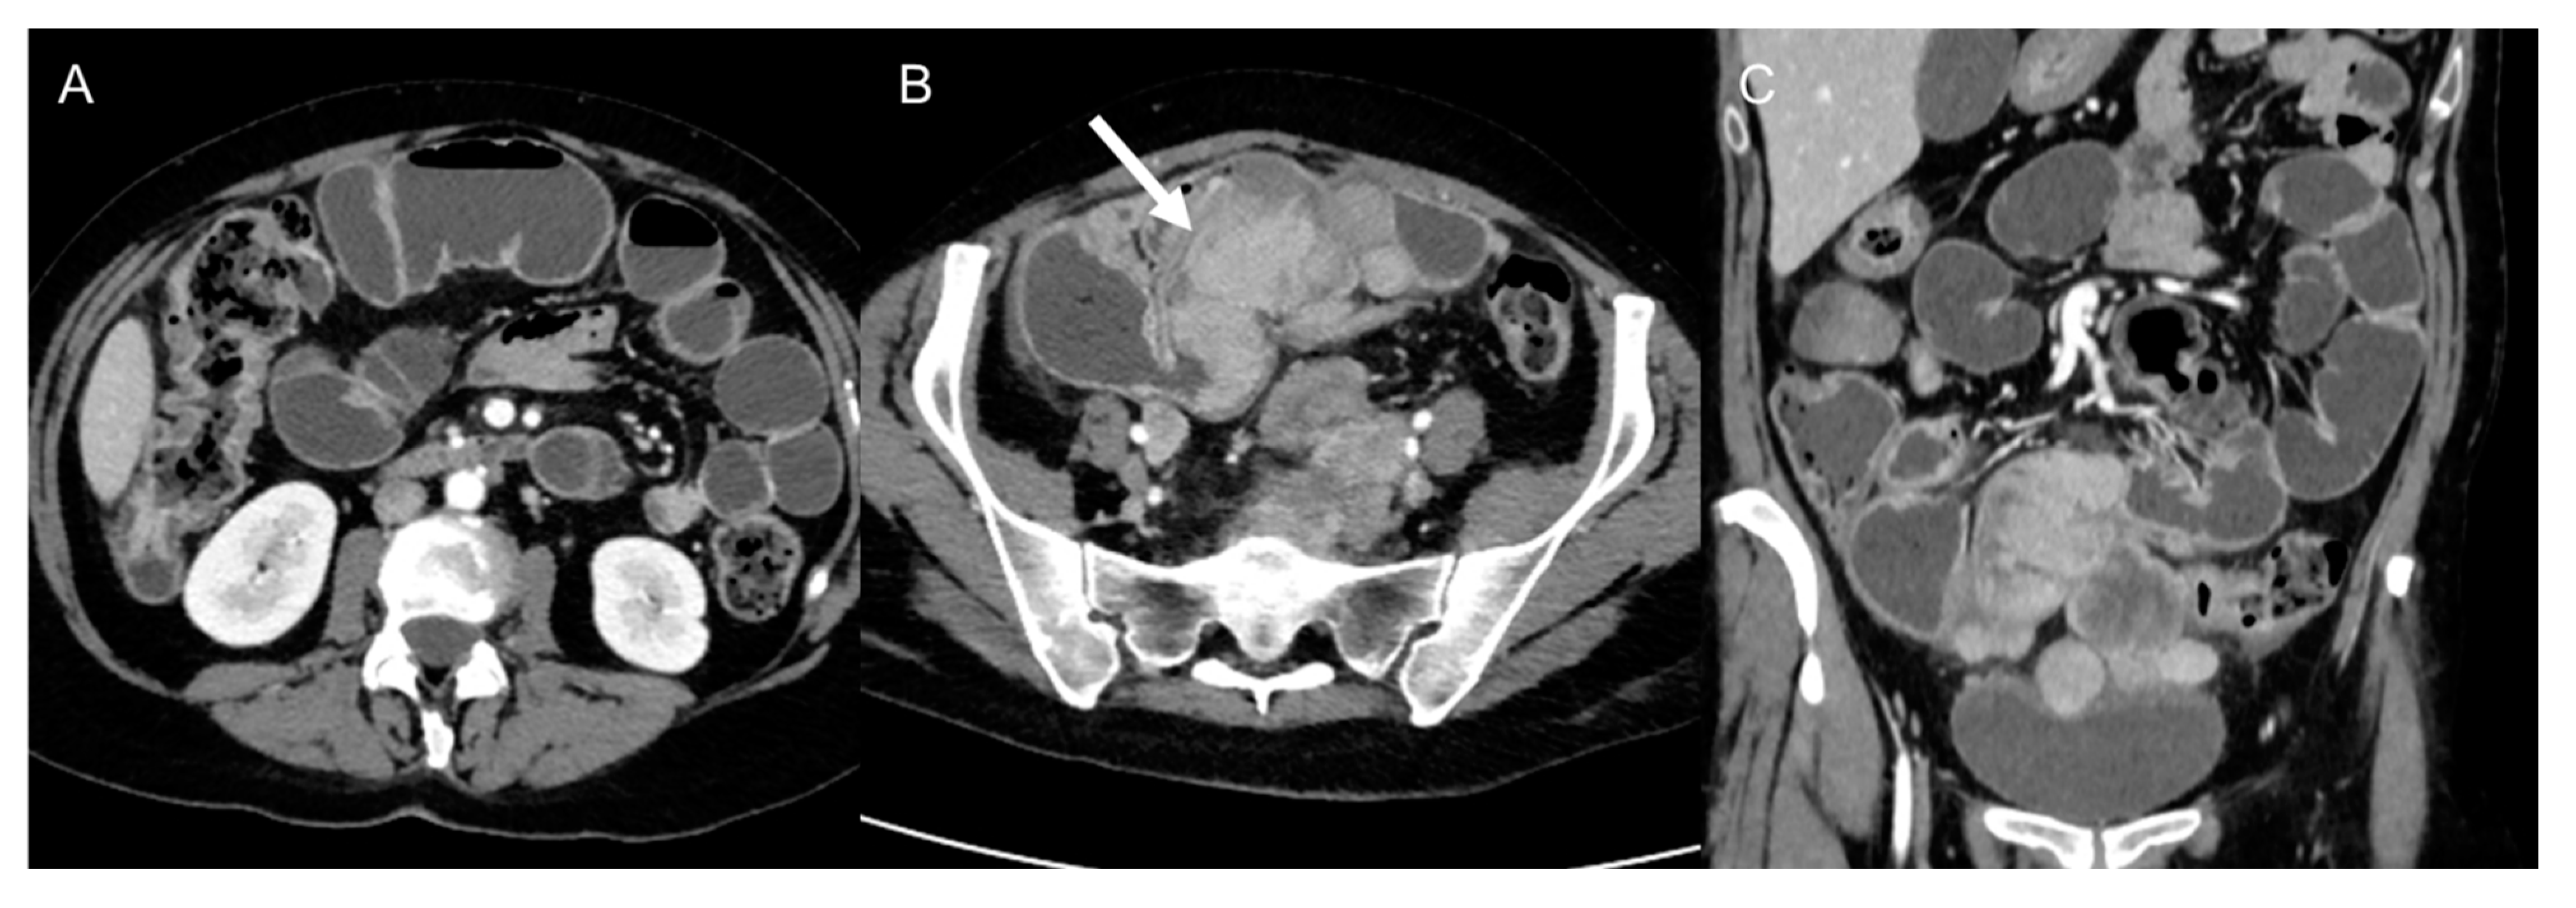

- Dedifferentiated liposarcomas (Figure 2) are high-grade tumors with poor prognosis. Characteristic features include heterogeneous nonlipomatous mass within, adjacent to, or surrounding a fatty mass [37,38]. There may be no evidence of fat-density tissue in up to 20% of cases, making the imaging diagnosis difficult [40]. Enhancing septa within the fatty portions are frequently seen [37]. Calcifications are rare (around 25% of cases) and are poor prognostic factors [39].

Figure 2. Dedifferentiated retroperitoneal liposarcoma in a 68-year-old man. Axial (A) and coronal (B) contrast-enhanced CT images in the venous phases show a 24 cm solid mass in the right retroperitoneal space, with internal necrotic areas and adjacent nodules (arrows). The lesion was histologically confirmed at biopsy.